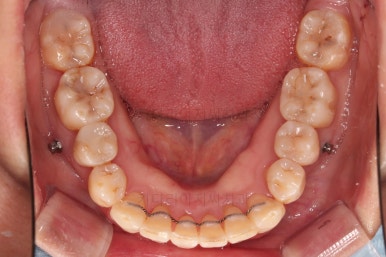

비발치 치료에서 핵심되는 장치가 미니스크류에요.

위 사진에서도 어금니쪽 잇몸 부위를 보시면 아주 작은 금속성 나사머리가 보이실건데요. 나사로 단단히 지탱해주고 치열을 뒤로 당겨주는 원리죠.

마무리 사진이에요.

치열이 매우 가지런해졌고, 틈도 없고, 앞니의 뻗친 느낌도 사라졌네요.

교합도 좋고요.